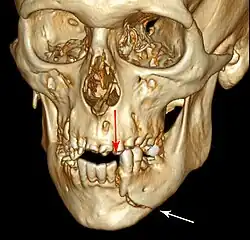

Injuries to supporting bone

This injury involves the alveolar bone and may extend beyond the alveolus.[5][6] There are five different types of alveolar fractures:

- Fracture of the maxilla: Le Fort fracture, zygomatic fracture, orbital blowout

Trauma injuries involving the alveolus can be complicated as it does not happen in isolation, very often presents along with other types of tooth tissue injuries.

Signs of dentoalveolar fracture:

- Change to occlusion

- Multiple teeth moving together as a segment and are normally displaced

- Bruising of attached gingivae

- Gingivae across the fracture line often lacerated

Investigation: Require more than one radiographic view to identify the fracture line.

Treatment: Reposition displaced teeth under local anaesthetic and stabilise the mobile segment with a splint for 4 weeks, suture any soft tissue lacerations.